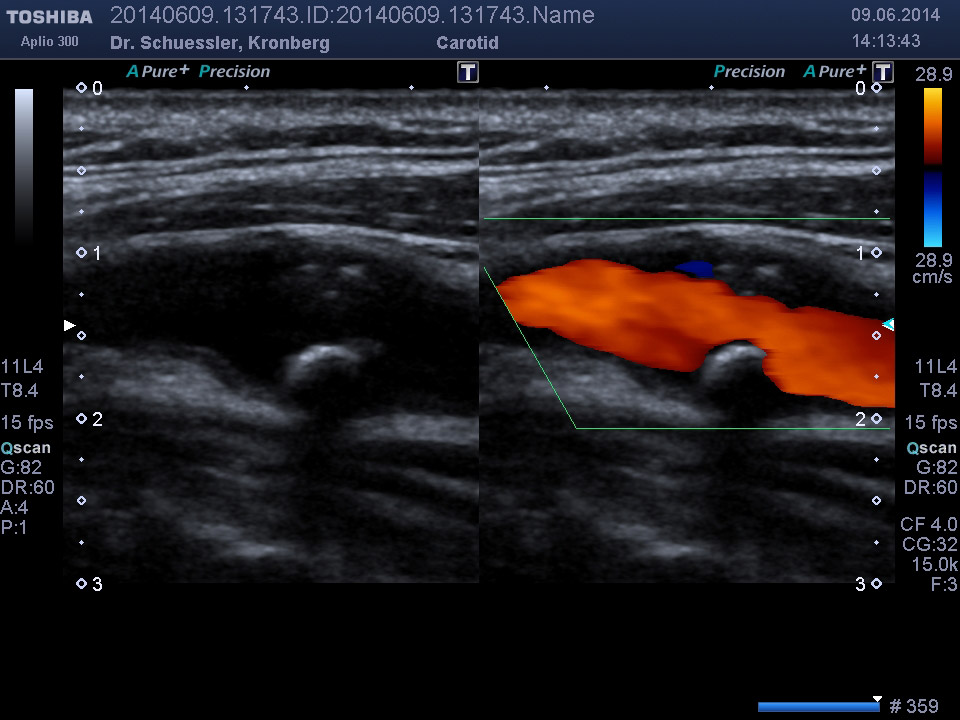

Duplex Gefäße (Duplexsonographie)

Die farbkodierte Duplexuntersuchung der Gefäße ist ein Ultraschallverfahren und gibt u.a. Auskunft über Verkalkungen, Einengungen, Verschlüsse oder Thrombosen im Bereich der Arterien und Venen.

Die Untersuchung wird angewandt zur Diagnostik von Verengungen in den hirnversorgenden Arterien, Erweiterungen (Aneurysmen) oder Verengungen der Bauchschlagader, Verengungen der Nierenarterien bei Bluthochdruck,  Venenthrombosen und zur Bestimmung des Gefäßrisikoprofils.